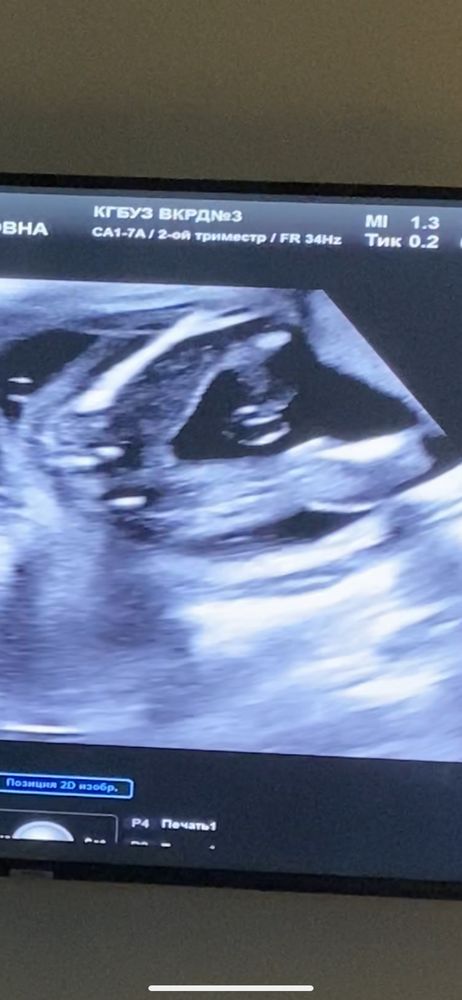

Второй скрининг 🤍

были уверены, что у нас мальчик) но нет, девочка 🥰